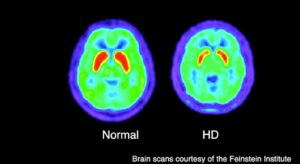

Scoperto un composto che rallenta la progressione della malattia di Huntington

Attualmente, non esiste alcun trattamento per arrestare la progressione della malattia di Huntington (HD), una malattia genetica che compromette lentamente…

Nuova scoperta sulla malattia di Huntington

I ricercatori dell’ Università della Florida hanno scoperto che il gene che causa la malattia di Huntington produce un “cocktail”…